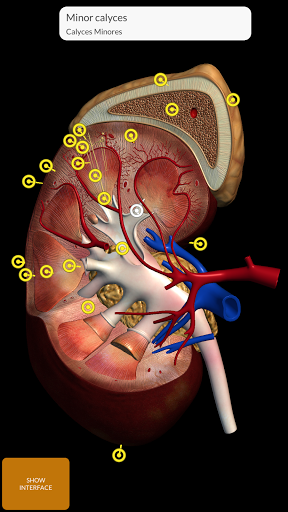

"Anatomía - Atlas 3D" permite estudiar la anatomía humana de forma fácil e interactiva.

A través de una interfaz sencilla e intuitiva es posible observar cada estructura anatómica desde cualquier ángulo.

Los modelos anatómicos 3D son especialmente detallados y con texturas de hasta una resolución de 4k.

La subdivisión por regiones y las vistas predefinidas facilitan la observación y el estudio de partes individuales o grupos de sistemas y las relaciones entre los diferentes órganos.

MODELOS ANATÓMICOS 3D

nervioso • Sistema respiratorio • Sistema digestivo • Sistema urogenital (masculino y femenino) • Sistema endocrino • Sistema linfático • Sistema ocular y auditivo CARACTERÍSTICAS • Interfaz sencilla e intuitiva • Rotar y hacer zoom en cada modelo en el espacio 3D • Opción para ocultar o aislar uno o varios modelos seleccionados • Filtro para ocultar o mostrar cada sistema • Función de búsqueda para encontrar fácilmente cada parte anatómica • Función de marcador para guardar vistas personalizadas • Rotación inteligente que mueve el centro de rotación automáticamente • Función de transparencia • Visualización de músculos a través de niveles de capas desde las superficiales hasta las más profundas • Al seleccionar un modelo o un pin, aparece el término anatómico relacionado • Descripción de los músculos: origen, inserción, inervación y acción • Mostrar/ocultar interfaz de usuario (muy útil con pantallas pequeñas) MULTILINGÜE • Los términos anatómicos y la interfaz de usuario están disponibles en 11 idiomas: latín, inglés, francés, alemán, italiano, portugués, turco, ruso, español, Chino, japonés y coreano • Los términos anatómicos se pueden mostrar en dos idiomas simultáneamente REQUISITOS DEL SISTEMA • Android 8.0 o posterior, dispositivos con al menos 3 GB de RAM Reversi